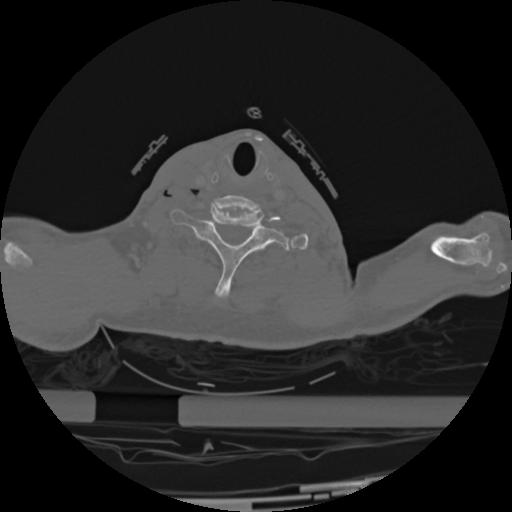

22 ANGIO,CE,Vol,0.5,ANGIO,,